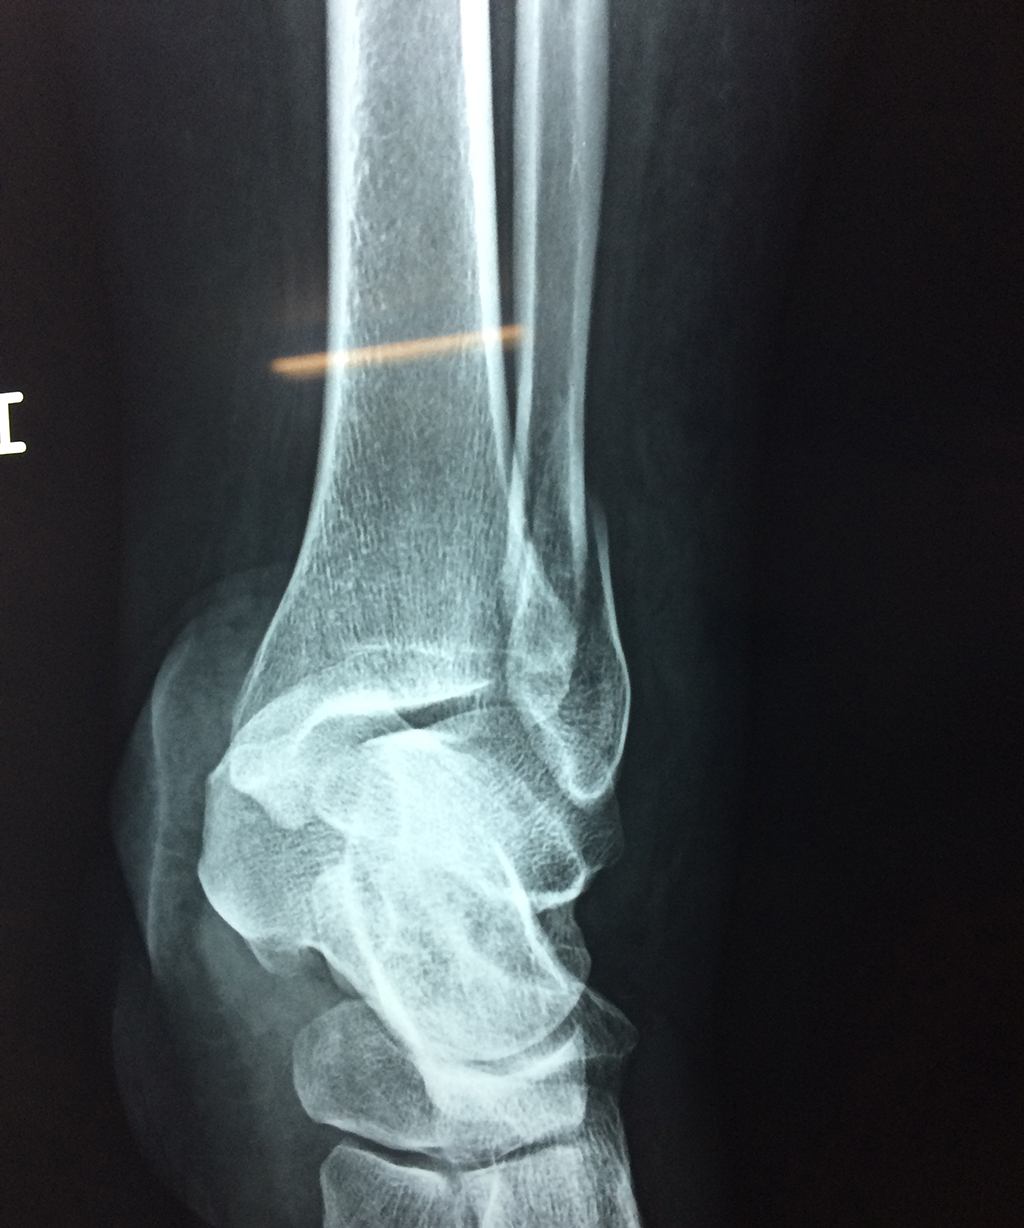

Una fractura de tobillo es la rotura de uno o más de los huesos del tobillo. Estas fracturas pueden ser:

- Parciales (el hueso está sólo parcialmente fisurado, no del todo).

- Completas (el hueso está perforado y está en 2 partes).

- Producirse en uno o ambos lados del tobillo.

Algunas fracturas de tobillo pueden requerir cirugía si:

- Los extremos de los huesos están desalineados entre sí (desplazados).

- La fractura se extiende hasta la articulación del tobillo (fractura intra-articular).